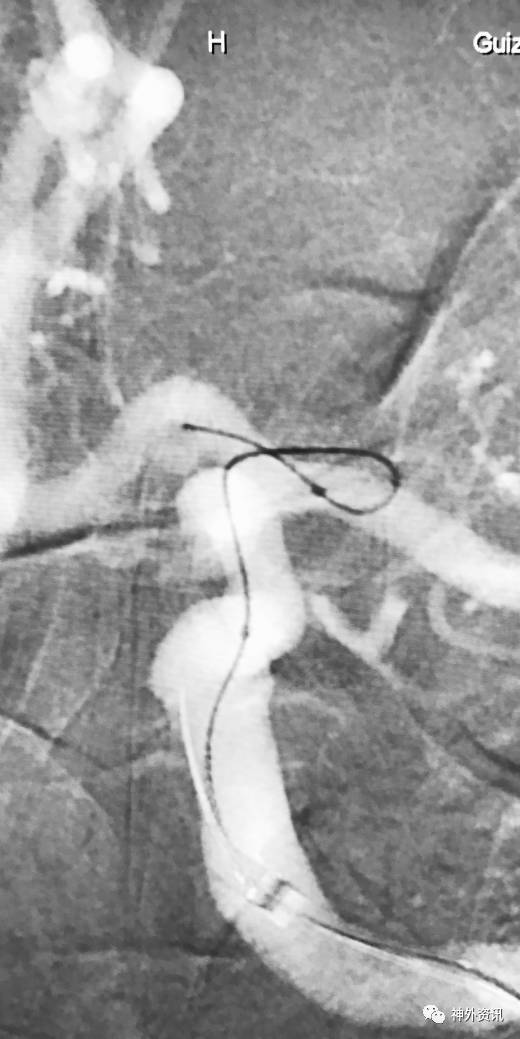

大C塑形

10mm以上的大动脉瘤:

(1)C型头端完全进入动脉瘤囊内,微导管的盘旋有利于均匀填塞

(2)避免微导管头端过早踢出

病例一